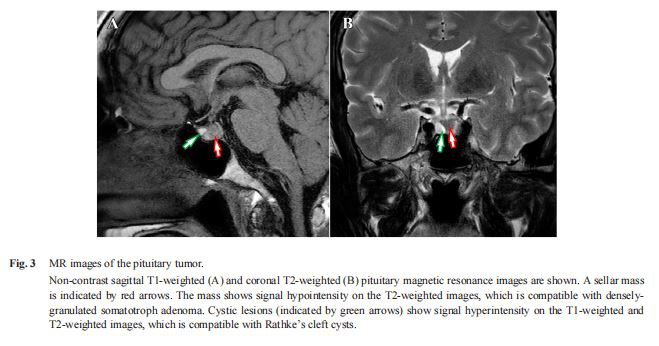

Data makmal mengenai kemasukan ditunjukkan dalam Jadual 1. Diagnosis akromegali disahkan oleh ciri klinikalnya seperti berikut: (i) tahap faktor pertumbuhan 1 (IGF-1) serum insulin ialah 718 ng/mL (normal julat rujukan: 87 hingga 245 ng/mL); (ii) paras GH serum telah dinaikkan pada garis dasar (8.16 ng/mL) dan tidak ditindas dengan sewajarnya (nadir: 6.72 ng/mL) semasa ujian toleransi glukosa oral 75 g; (iii) dan MRI pituitari mendedahkan jisim bintang 9 mm diameter [13]. Jisim menunjukkan keamatan isyarat yang rendah pada imej berwajaran T{14}} dan mempunyai lesi hiperintensis yang menunjukkan sista celah Rathke (Gamb. 3). Radiografi buku lali menunjukkan ketebalan pad tumit (23 mm), yang konsisten dengan diagnosis akromegali.

Tiga bulan selepas kemasukan, pembedahan transsphenoidal untuk tumor pituitari dilakukan. Tumor itu secara intraoperatif didapati berwarna putih. Di samping itu, lesi sista dalam tumor pituitari mengandungi cecair mukus yang kurang berwarna dan putih dengan lapisan epitelium bersilia nipis, yang mencadangkan sista sumbing Rathke apabila dipertimbangkan dengan penemuan MRI [14]. Pemeriksaan patologi tumor mendedahkan sel-sel seperti lembaran dengan nukleus bujur dan sitoplasma asidofilik atau amfofilik, yang konsisten dengan adenoma pituitari (Rajah 4A, 4B). Imunostaining untuk GH dan PRL adalah positif (Rajah 4C, 4D) dan imuno-histokimia anti-Cytokeratin (CAM 5.2) menunjukkan terutamanya corak perinuklear filamen keratin, menunjukkan ciri-ciri struktur yang serupa dengan adenoma somatotroph berbutir padat (Rajah 4E) , selaras dengan corak isyarat hipointense pada imej MRI berwajaran T2-(Gamb. 3B) [15, 16]. Indeks pelabelan Ki{17}} adalah kurang daripada 5 peratus (Gamb. 4F). Tahap serum GH dan IGF{{20}} selepas pembedahan telah dinormalisasi (masing-masing 0.92 ng/mL dan 170 ng/mL), menunjukkan kejayaan pembedahan pembedahan adenoma pituitari yang menghasilkan GH. Tiga bulan selepas pembedahan, tahap HbA1c dan UPCR telah menurun dengan ketara (masing-masing 5.7 peratus dan 1.09 g/GCR), tetapi eGFR tidak berubah (34 mL/min/ 1.73 m2 ) (Rajah 1).